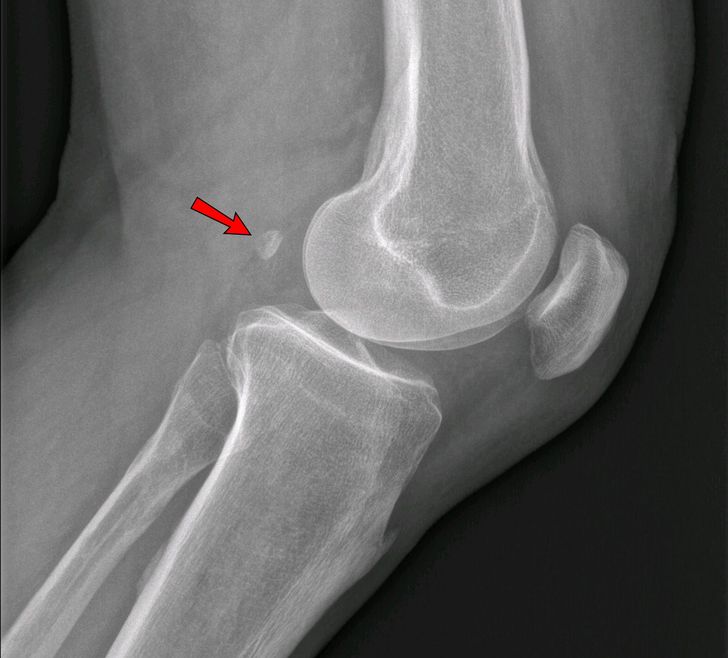

У 39 % людей в колене есть лишняя кость — фабелла. Еще 100 лет назад только 11 % людей имели эту кость. Встречается она чаще у мужчин, а также у пожилых людей. Функция дополнительной кости неизвестна, однако из-за нее часто появляются боли в коленях.